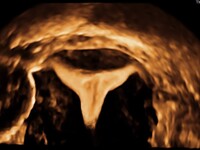

- υδρο-υπερηχογραφία με έγχυση φυσιολογικού ορού, ώστε να ελεγχθεί λεπτομερώς η ενδομήτρια κοιλότητα.

Για τους λόγους αυτούς, τα τελευταία χρόνια αναπτύχθηκε η υστερο-σαλπιγγογραφία με τη χρήση υπερήχων (HyFoSy), μια σύγχρονη μέθοδος με αξιοπιστία παρόμοια με την κλασική σαλπιγγογραφία, χωρίς όμως τα μειονεκτήματα της παλαιάς μεθόδου.